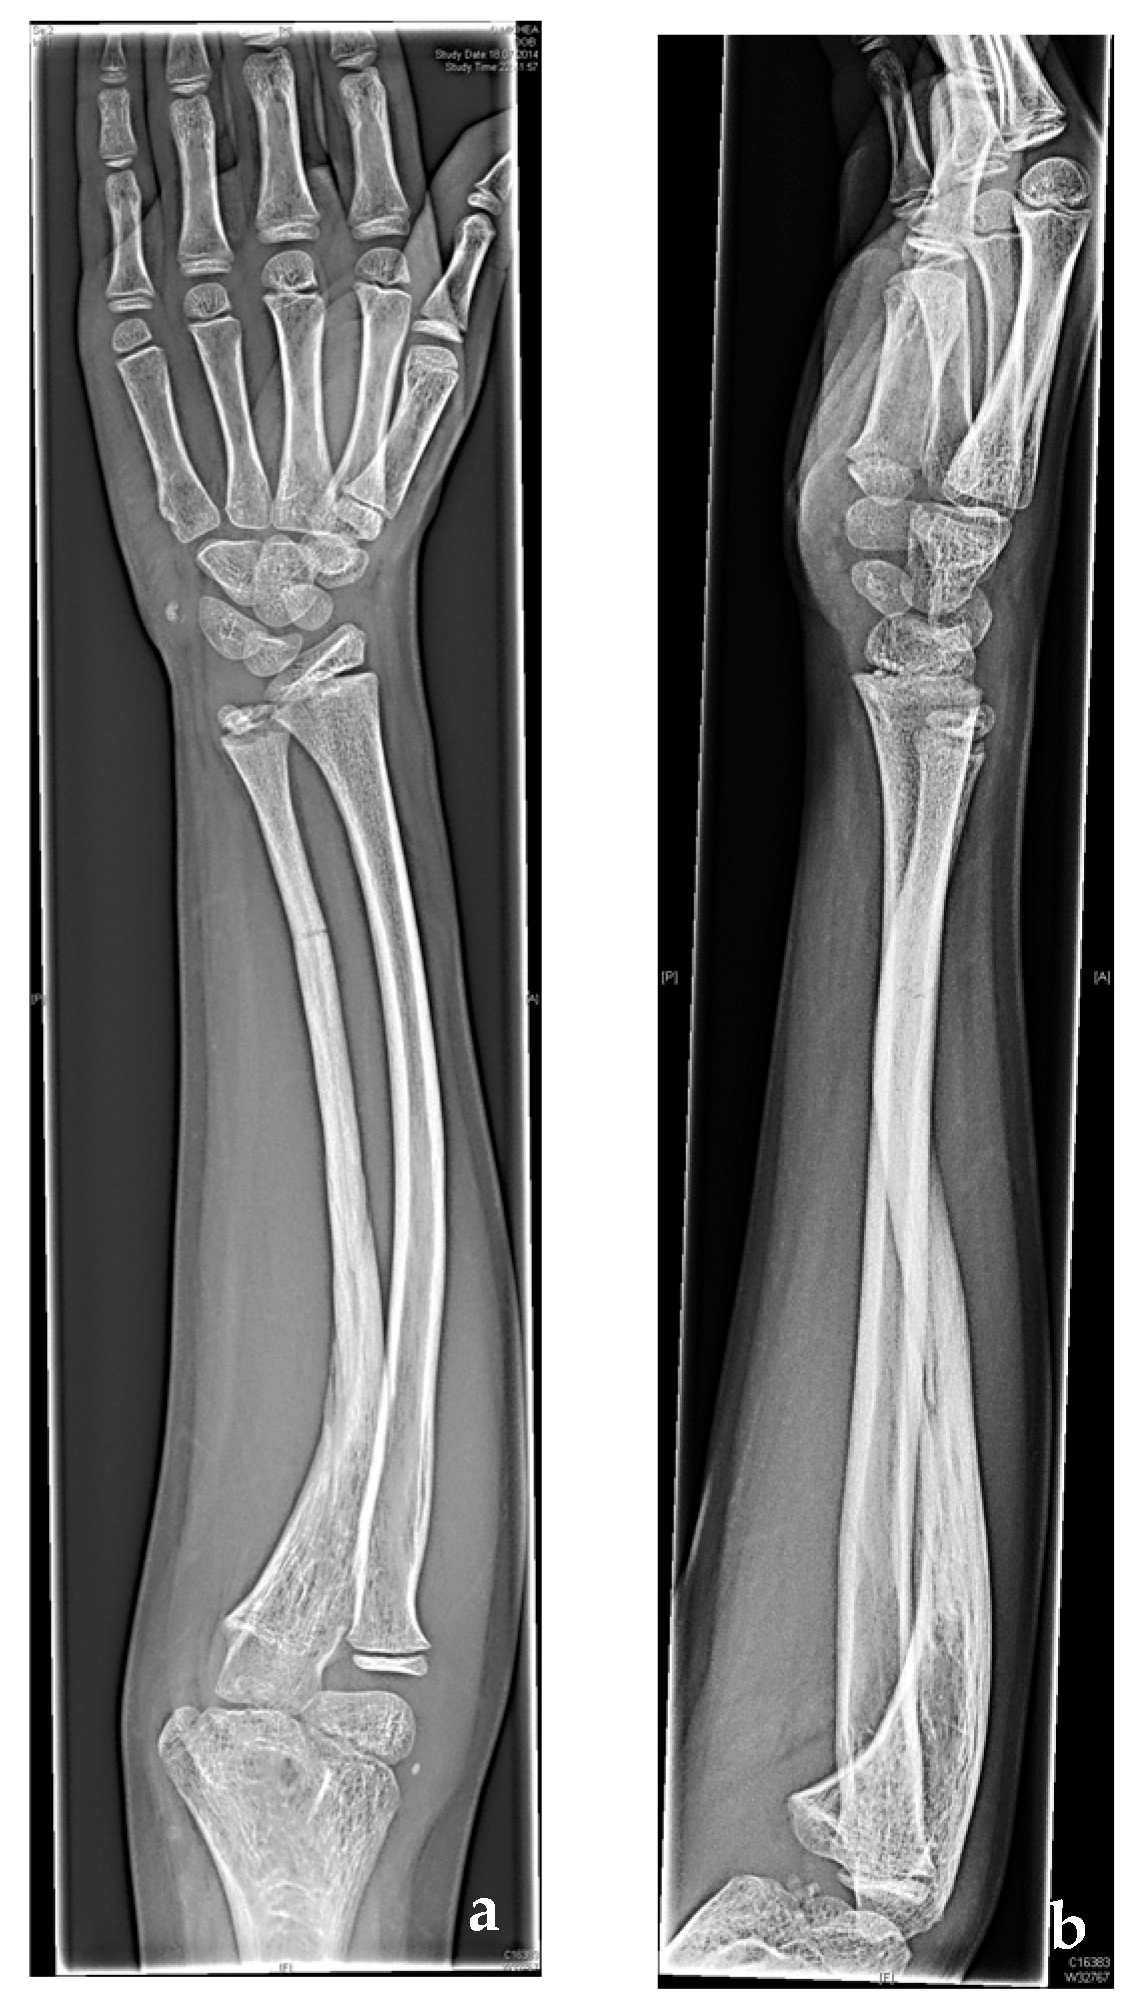

Nonunion ulnar fracture as a result of a remote injury BMJ Case Reports Non Union Radiology • obliques may be helpful for radiographic diagnosis of nonunion • ct can be helpful but metal artifact can make it. Identify the etiology and epidemiology of nonunion of bone medical conditions and emergencies. Web this case shows abnormal fracture healing in the tibia and fibula with pseudoarticulation formed in the tibial aspect. Non Union Radiology.